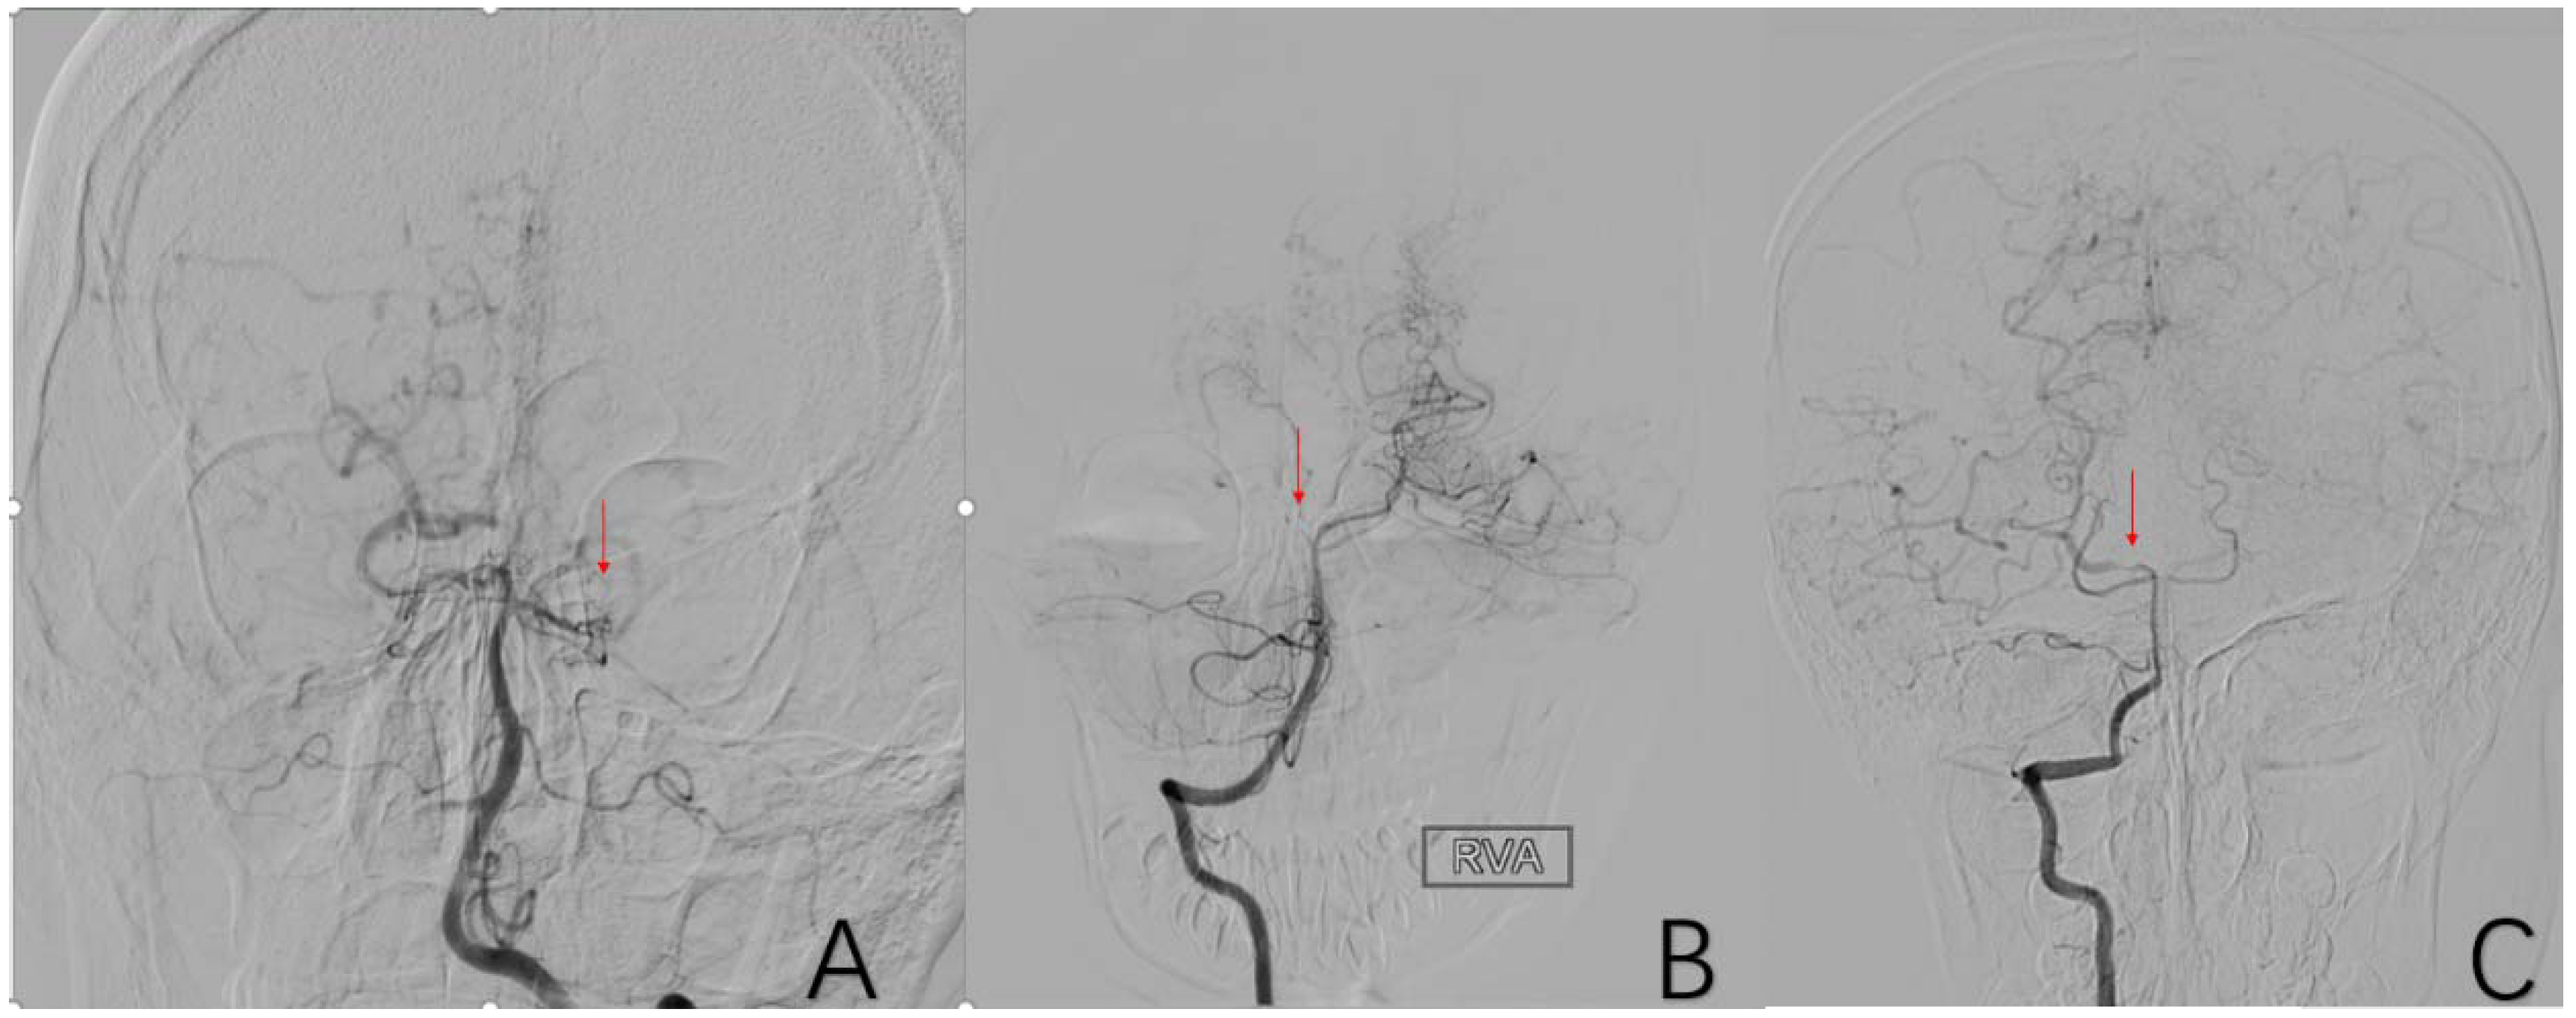

2.3.10. Factor 5 Posterior Circulation Compensation

2.3.11. Factor 6 Unstable Compensation

2.3.12. Factor 7 Extracranial Arterial Compensation